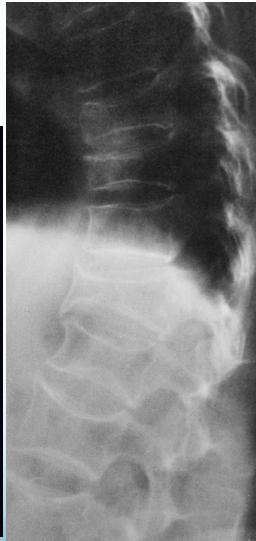

Radiographic features:

The changes of osteoporosis are best seen in the spine (Lateral thoracic and lumbar spine x-ray )

- Decreased bone density

- Loss of normal bony trabecula Dual energy x-ray absorptiometry (DEXA) is the gold standard technique for the diagnosis of osteoporosis

Decreased bone density in osteoporosis

X-ray lumbar spine (lateral view) of a patient with osteoporosis

The vertebrae have a low-density appearance as a result of the loss of trabecular bone, and the cortical outline of each vertebra appears accentuated. Z

Other potential findings on a spine radiograph in osteoporosis include an abnormal trabecular pattern and biconcave or compressed vertebral configuration.